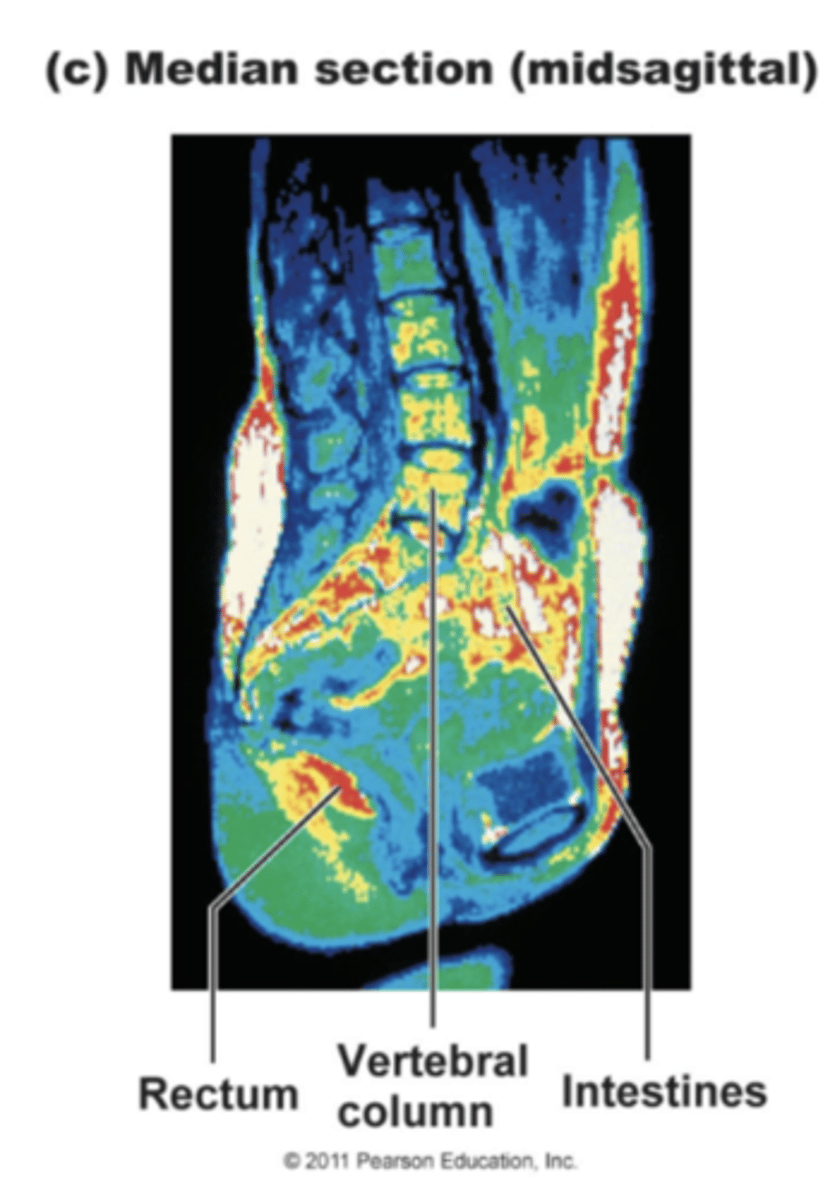

Sagittal Section

A sagittal, median or midsagittal plane is cut down the long length of the body. The body is split into right and left halves. If the plane is exactly in the center, then it is considered to be midsagittal.